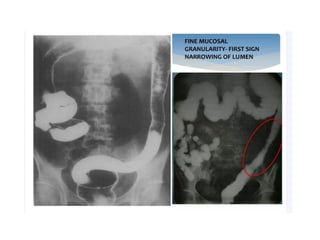

Ulcerative Colitis

• Ulcerative colitis (UC) is a characterized by

superficial inflammation involving the colon.

• The colonic involvement in UC is symmetric and

contiguous.

• Rectum is involved in almost all cases with varying

length of proximal colonic involvement sometimes

involving the entire colon (pancolitis)

• Occasionally, terminal ileum can be affected and

becomes edematous and dilated when the entire

colon is involved and is called backwash ileitis

• Lead pipe sign in chronic UC. Barium study images (A and B) of a patient with

ulcerative colitis showing diffuse luminal narrowing and loss of haustrations

(thin arrow) involving the entire colon without any skip areas. This

featureless appearance of colon in chronic UC is known as lead pipe sign.